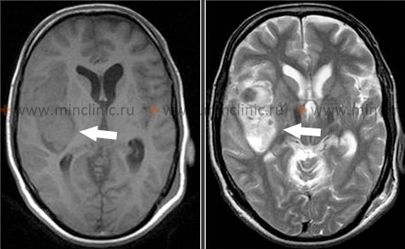

თალამუსის ჰიპერტენზიული ინტრაცერებრული სისხლჩაქცევები

თალამუსში (ჰიპერტენზიული სისხლდენების კიდევ ერთი ხშირი ლოკაცია) დაწყებული სისხლჩაქცევა, როგორც წესი, იწვევს კონტრალატერალურ ჰემიპლეგიას ან ჰემიპარეზს მიმდებარე შიგნითა კაფსულის კომპრესიის ან ჩართვის გამო [1, 2]. გამოხატული თვისება ხშირად არის მგრძნობელობის კონტრალატერალური ნახევრად დაკარგვა (ჰემისენსორული დანაკარგი), რომელიც გავლენას ახდენს ყველა სენსორულ მოდალობაზე (ტკივილი, ტემპერატურა, პროპრიოცეფცია, ტაქტილური შეგრძნება), რაც ასახავს თალამუსის, როგორც მთავარი სენსორული გადამრთველი ბირთვის, როლს [1].

დომინანტური ნახევარსფეროს თალამუსის დაზიანებებმა შეიძლება გამოიწვიოს ენის/მეტყველების დარღვევები (დისფაზია ან აფაზია), რაც ხშირად ხასიათდება გამართული მეტყველებით პარაფაზიული შეცდომებით, მაგრამ შედარებით შენარჩუნებული გამეორების უნარით, ზოგჯერ თან ახლავს მეხსიერების დეფიციტი [1]. სისხლჩაქცევამ არადომინანტურ თალამუსში შეიძლება გამოიწვიოს კონსტრუქციული აპრაქსია და სივრცითი უგულებელყოფა (აპრაქტოაგნოზია) [1]. ჰომონიმური მხედველობის ველის დეფექტები (გავლენას ახდენს მხედველობის ველის ერთსა და იმავე ნახევარზე ორივე თვალში) შეიძლება მოხდეს თალამუსის მახლობლად მდებარე გზების ჩართვის გამო, მაგრამ შეიძლება ნაწილობრივ გაუმჯობესდეს [1]. თალამური სისხლჩაქცევის გავრცელება ინფერომედიალურად სუბთალამური რეგიონისა და შუა ტვინის ზედა ნაწილისკენ ხშირად იწვევს დამახასიათებელ ოკულომოტორულ (თვალის მოძრაობის) დისფუნქციებს, მათ შორის [1]:

- ვერტიკალური მზერის დარღვევა (განსაკუთრებით ზევით მზერის პარეზი)

- თვალების ქვემოთ დევიაცია მოსვენებულ მდგომარეობაში ("ჩამავალი მზის სიმპტომი")

- გუგის პათოლოგიები: ანიზოკორია (არათანაბარი გუგები), გუგები ხშირად მცირე ან საშუალო ზომისაა და სუსტად რეაგირებენ სინათლეზე

- Skew დევიაცია (თვალების ვერტიკალური ასიმეტრია)

- დარღვეული კონვერგენცია

- ფსევდო-აბდუცენსის პარეზი (დარღვეული თვალის გარეთ მოძრაობა, რომელიც ბაძავს მეექვსე ნერვის პარეზს მზერის გზების ჩართვის გამო)

- რეტრაქციული ნისტაგმი (ზევით მზერის მცდელობისას თვალები იწევს უკან ბუდეებში)

სხვა პოტენციური ნიშნები მოიცავს იპსილატერალურ პტოზს და მიოზს (ჰორნერის სინდრომის ნაწილი, თუ სიმპათიკური გზები კომპრესირებულია), ქუთუთოს შეშუპებას ან იშვიათად, მუტიზმს (საუბრის უუნარობას), განსაკუთრებით ორმხრივი ან დომინანტური თალამუსის ჩართვისას [1].

- თალამური სისხლჩაქცევა: მზერის ქვემოთ დევიაცია, დარღვეული ვერტიკალური მზერა და გუგის სხვადასხვა პათოლოგიები (ხშირად მცირე, სუსტად რეაქტიული).